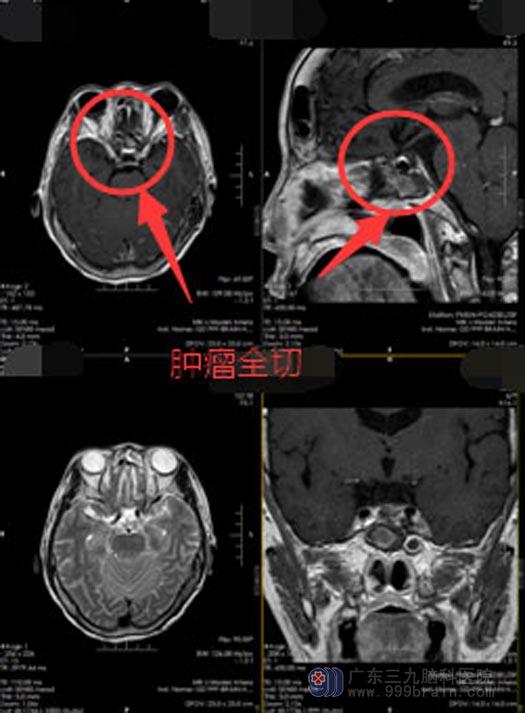

陈阿姨做梦也没想到脑袋里竟然有个肿瘤,家人也认为需要慎重考虑后再决定是否进行手术治疗。回家后,陈阿姨的异常症状越来越严重,她再次来到医院入住神经外五科,陈阿姨的诊断明确,有手术指征,家人同意经鼻蝶行鞍区占位切除术,不开颅就能除掉占位。全麻下行“内镜经鼻蝶鞍区rathke囊肿切除术+颅底重建术”,双侧鼻腔暴露蝶窦开口,切除部分蝶窦粘膜,全层切开硬脑膜,见肿瘤灰白色,质软,正常垂体组织位于前方,囊肿全切,无脑脊液漏,术程顺利。

术后,陈阿姨说头痛头晕症状好转,眼睛看东西也不会有重影了。

▲手术后